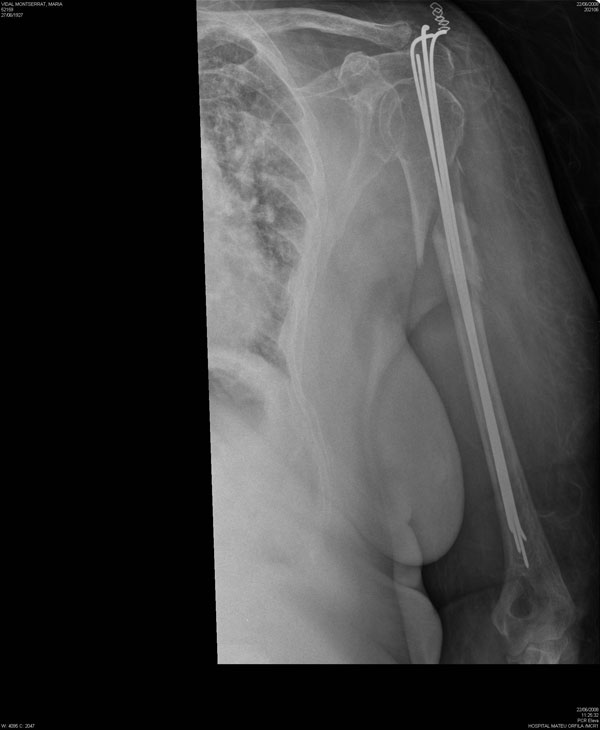

Fractura de diáfisis de húmero.

Fractura de húmero tras osteosíntesis con clavo gamma.